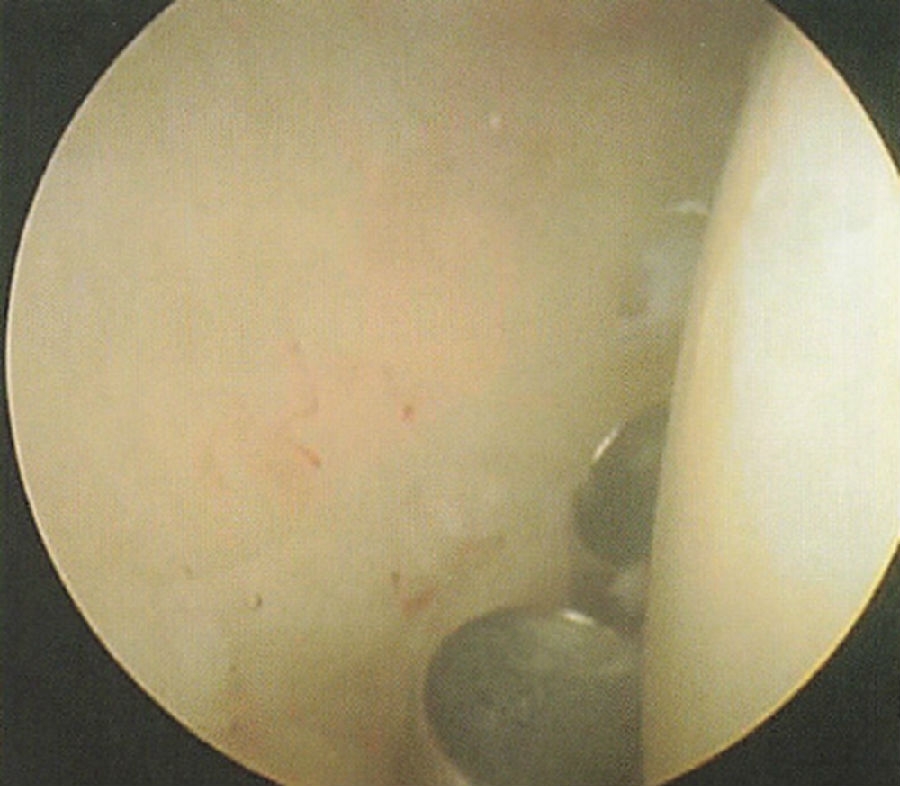

股骨大转子前缘的前上方约1cm,穿刺方位为偏向头侧0°~15°,向后20°~30°。前外侧入路穿过臀中肌,到达髋关节前方关节囊(图51-69A),其最为接近的神经血管结构为上神经和坐骨神经。前外侧入路可以观察中央室(尤其是前和上),清理工作通道或置钉,观察外周室及操作通道(图30-5)。

图51-69A 标准入路:前外侧入路

图30-5 70°镜头下经前外侧入路观察,可见左侧为前上的盂唇损伤,右侧为股骨头,以及位于盂唇和股骨头之间的间室(“V”形)